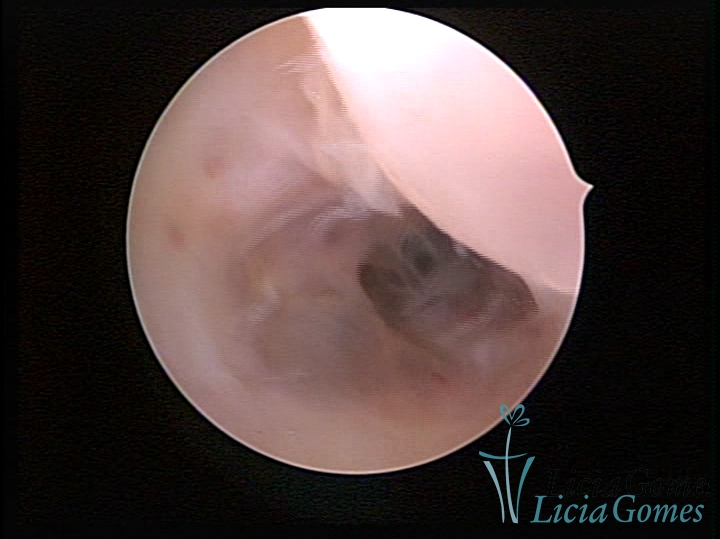

FIBROUS SYNECHIA

• SINÉQUIA TIPO FIBROMUSCULAR